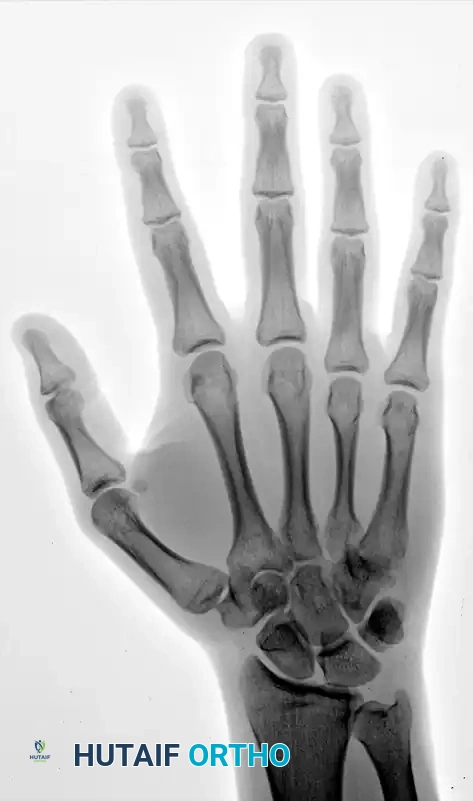

Standard posteroanterior (PA), lateral, and oblique radiographs are mandatory. However, the overlapping anatomy of the carpus can obscure subtle subluxations.

FIGURE 67-30 B-D: Posteroanterior, Lateral, and Oblique radiographic views demonstrating the dorsal dislocation of the fourth and fifth carpometacarpal joints.

> CLINICAL PEARL: Always obtain a true lateral radiograph of the hand. The metacarpal shafts should align perfectly parallel. Any dorsal divergence of the 4th or 5th metacarpal shafts relative to the 3rd metacarpal is highly indicative of a CMC dislocation. If plain films are equivocal, a CT scan is the gold standard for evaluating articular comminution and subluxation.